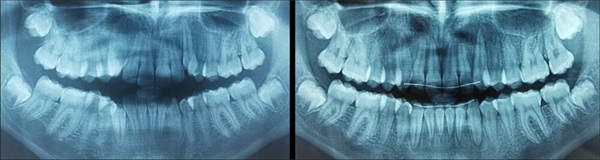

Panoramic radiographs (Fig. 7) and maxillary occlusal views show the corrected orthoerupted position of the canines with root parallelism in 71 days.

Fig. 7: Panoramic radiographs before and after